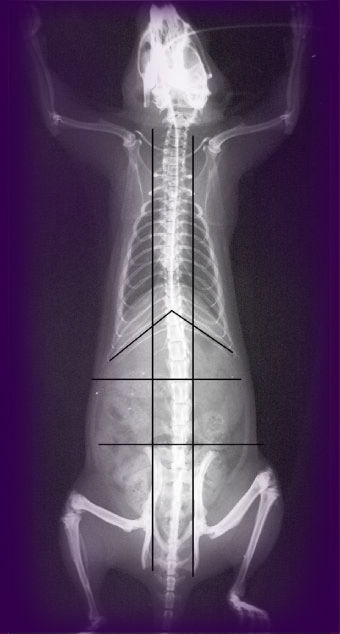

So Tsafnat placed her rat bone between two clamps in a compression chamber. The apparatus was small enough to fit in the University of Sydney’s newly purchased Micro-CT scanner, enabling her to scan the bone before and after it was put through its paces.

“We had the exact geometry, and all the boundary conditions were set up. Our only unknown was the material properties themselves,” says Tsafnat. The model bone was then squashed to reveal breaking points. Then the real bone was squashed until it really broke.

Thankfully, the experiment had a happy ending (though not, perhaps, for the rat bone . . . or the rat). Tsafnat’s model was dead on, validating the assumptions made for many a scanned bone of yesteryear. The fracture points it predicted were indeed the very places where the real bone fractured.